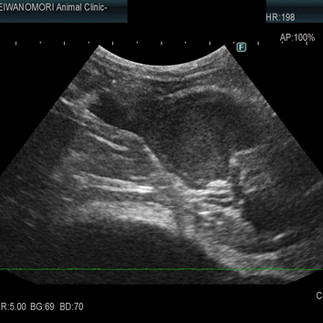

身体検査にて、発熱と腹部にシコリ(腫瘤)を触知しました。

その後、血液検査、腹部超音波検査、腹腔内の腫瘤の細胞診検査(FNA)、腫瘤から採取した細胞の猫コロナウイルス検査をさせて頂きました。

また治療1週間で腹腔内の腫瘤サイズは半分になり、2週間後にはさらに小さくなっていました。